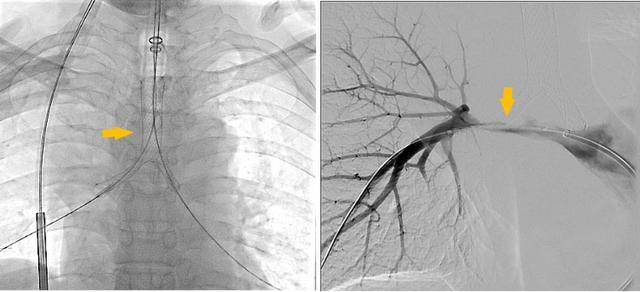

同期置入支架后狭窄明显改善